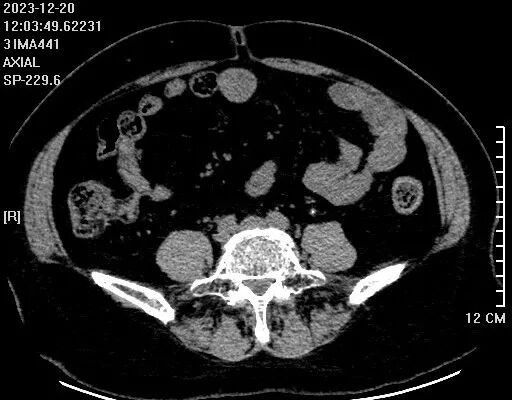

患者左側(cè)輸尿管上段有一個2*3mm小結(jié)石

左腎重度積水腫像個水球,腎皮質(zhì)薄如紙,預(yù)示著它已經(jīng)沒有什么功能了